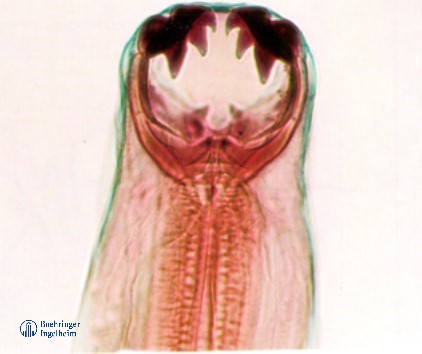

咬住腸道不放的寄生蟲▸鉤蟲

鉤蟲是腸道寄生蟲的狠角色,會用牙齒咬住腸道吸血寄生,使腸道黏膜受損發炎、糞便中有血或拉肚子,嚴重時可能造成貧血、虛弱。